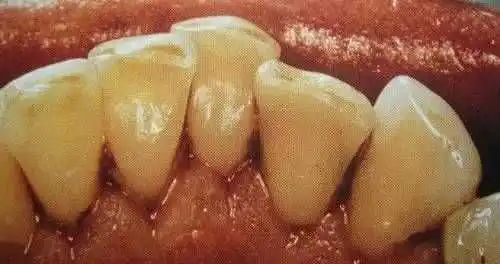

洗牙(洁治)后,洁白如一

洗牙(洁治)后效果很明显